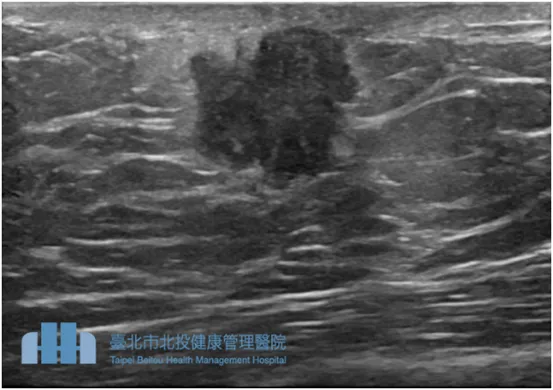

錢政平分享曾收治一名45歲林姓男子,每晚習慣喝1-2杯酒,屬於肥胖體型、BMI為32,也因肥胖導致男性女乳症。某天他突然發現,右胸乳頭上方似乎有一個小腫塊,就醫透過胸部超音波檢查發現該腫瘤邊緣明顯呈現不規則型態,進一步檢查確認罹患乳癌。